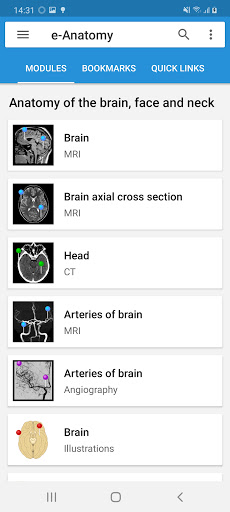

New : You can now filter the modules by region or by content type so you can find the module you are looking for much faster.

-Two new modules : Brain - TOF and Brain Angiography, Atlas of normal neurovascular anatomy of arteries of the brain on a cerebral angiogaphy.-The interface has been reworked.-A new tab named "QuickLinks" is available, dispatching modules in sections of the human body and allowing you to fast travel to the modules you are looking for.-Fixed small bugs.